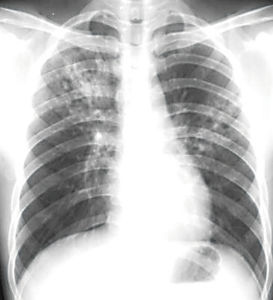

影像學檢查

胸部X線檢查為診斷肺結核的必備手段,可判斷肺結核的部位、範圍、病變性質、病變進展、治療反應、判定療效的重要方法 。